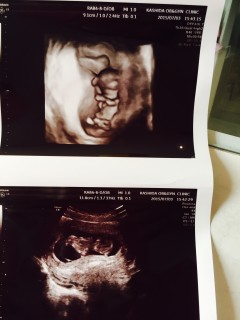

下の写真の時は丁度寝返りをうってて そっぽ向かれちゃった感じかな? でも上の写真の時はパンチしたりキックしたり なんだかシャドーボクシングしてるみたいで 可愛かったです(((o(*゜▽゜*)o))) 背は4.3cmくらい。 すくすくと順調に育ってて、 元気に動いてて一安心です。